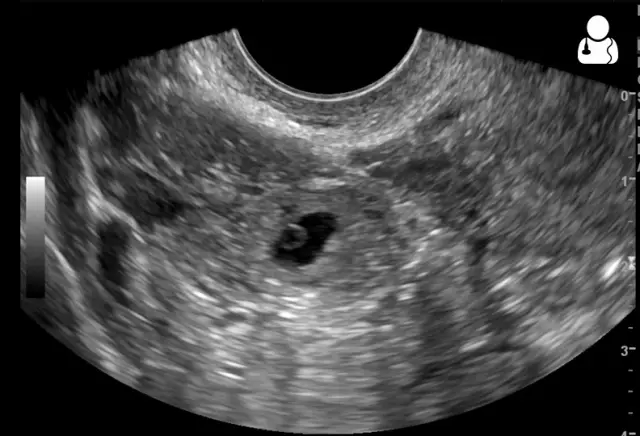

Kompletni ultrazvučni pregled može se obaviti u ordinaciji Hećimović.